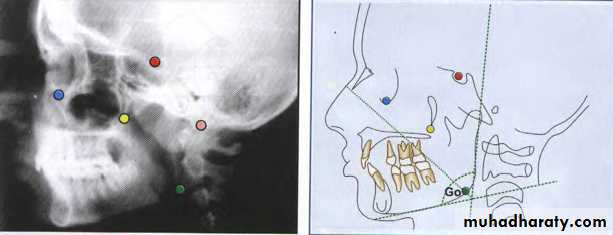

Cephalometric landmarks

A conspicuous point on a cephalogram that serves as a guide for measurement or construction of planes – JacobsonRequisites for a landmark

Should be easily seen on the x ray filmBe uniform in outline

Easily reproducible

Should permit valid quantitative measurement of lines and angles

Lines and planes should have significant relationship to the vectors of growth

Lateral Cephalometric

• Hard tissue landmarks

BILATERAL LANDMARKS

Gonion (Go)

Gonion is the most posteroinferior point at the angleof the mandible. It may be determined by inspection

or by bisecting the angle formed by the junction of the

ramal and mandibular lines, and extending this

bisector through the mandibular border.